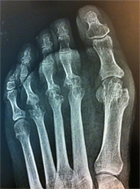

Mme R., née en 1961, a été hospitalisée en hôpital de jour le 19/10/2011, pour bilan de sa polyarthrite : facteur rhumatoïde positif et anti-CCP très positifs (2065).

Elle présentait, entre autres, des ténosynovites des pieds sans aucune érosion osseuse ni sur les radiographies standards ni sur l’IRM.

Malgré l’insistance et les explications de l’équipe soignante, Mme R. refuse les traitements de fond proposés et désire s’orienter vers des « biotraitements ».

Elle est revue avec une radiographie des pieds en mai 2013.